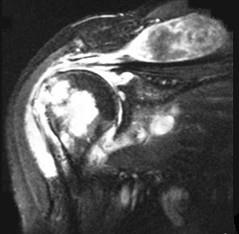

问题 女,71岁,有多年的系统性红斑狼疮病史,高剂量的类固醇服用史,左肩痛,请结合图像,选出最可能的诊断 ( )

选项 A、肱骨头缺血坏死 B、肩关节结核 C、类风湿关节炎 D、骨纤维肉瘤 E、化脓性关节炎

答案 B